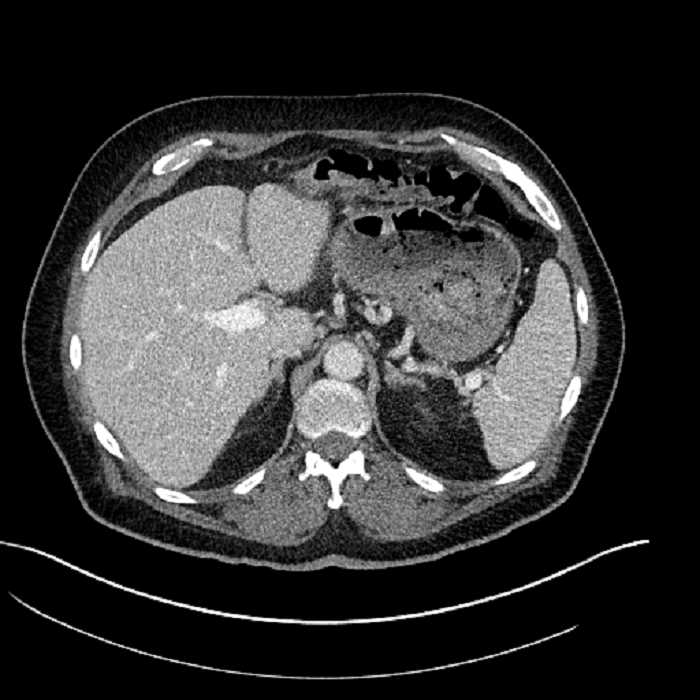

• Large fluid density structure in hepatic segments 7 and 8 measuring 10 x 7 x 7 cm with internal septation and circumferential ill-defined low density compatible with edema

• Peripherally enhancing subcapsular collections along the anterior margin of the left hepatic lobe measuring 3 x 1 cm and 2 x 1 cm

• Clearly marginated fluid density structure in segment 7 and several other scattered tiny hypodensities, which likely represent cysts

Acute sigmoid diverticulitis complicated by a small contained perforation and a large abscess in the right hepatic lobe. Additional small subcapsular abscesses along the anterior margin of the left hepatic lobe.

• The classic CT imaging appearance is a double target sign with internal low density surrounded by an internal enhancing rim (capsule) and a low density external rim (edema)

Hepatic abscess showing the double target sign with low density internally surrounded by a thin inner enhancing rim (red arrow) and ill-defined outer low density rim (yellow arrow). Blue arrow indicates an internal septation. Red arrows: additional smaller subcapsular abscesses. Red arrow: focal contained perforation associated with diverticulitis.